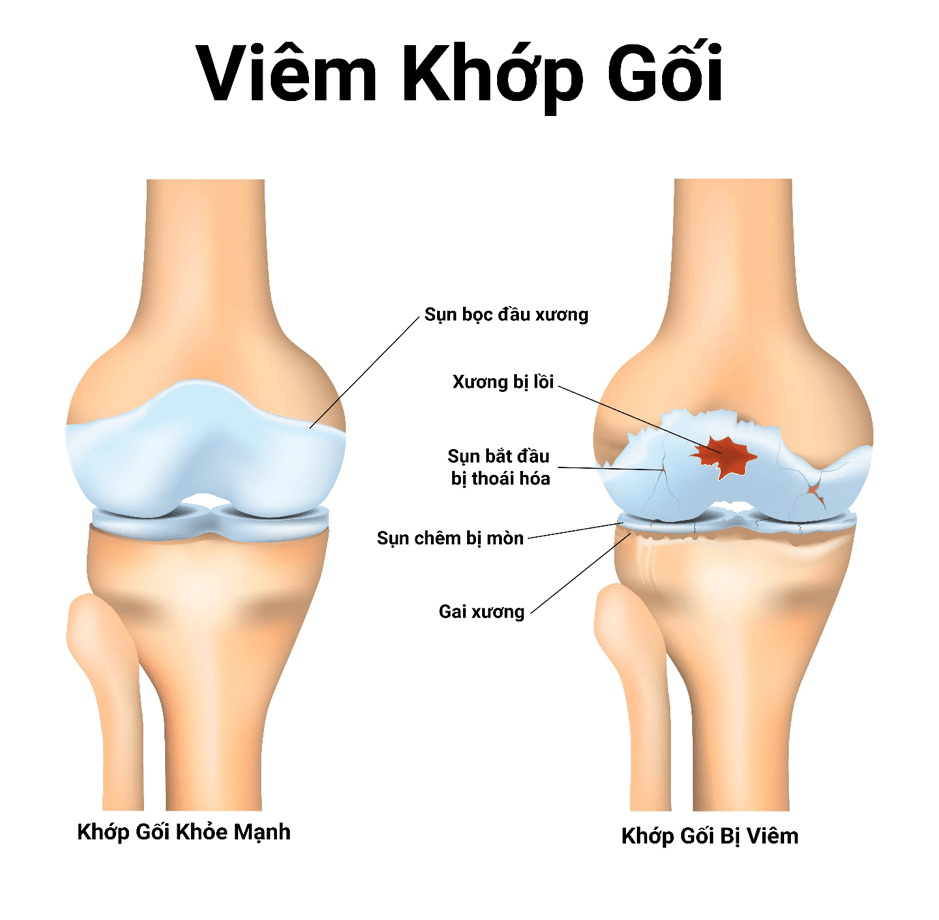

Viêm khớp gối

8. Thoái hóa khớp gối

Đây là loại viêm khớp gối phổ biến nhất, là nguyên nhân hàng đầu gây đau đầu gối ở người sau tuổi 50. Tình trạng này xảy ra khi sụn đầu gối bị thoái hóa dần theo thời gian, làm cho khớp gối bị đau và sưng lên khi cử động.